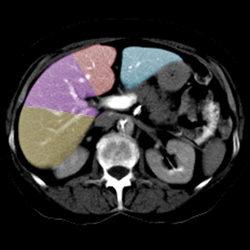

Liver anatomy

Segmental Anatomy of Liver